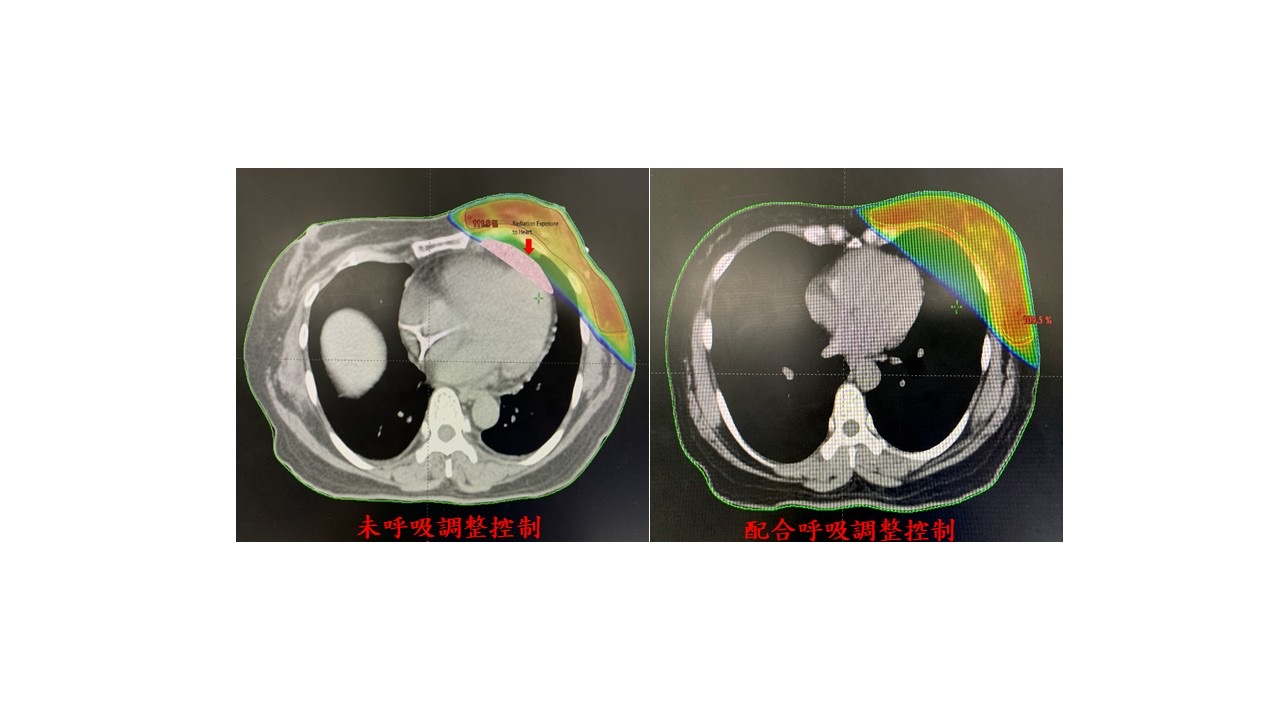

陳女士確診為第一期左側乳癌個案,由於她需兼顧工作、家庭,以及保有生活品質,國軍臺中總醫院放射腫瘤科主任劉珉玥醫師,為陳女士製作個人化放射線治療計畫,接受 「乳癌低分次放射線治療」合併「呼吸調控精準放射線治療技術」 ,將原先需長達六週的療程,縮短至4 週(約 20 次),大幅減少病人需醫院的時間,且透過即時呼吸調控系統(RGSC)監測呼吸週期,僅在深吸氣並短暫閉氣的時間進行照射,讓胸腔內正常組織與腫瘤拉開距離,大幅減少心臟與肺臟接受輻射照射的劑量,進一步降低長期心血管併發症的風險。

該院放射治療中心採用 TrueBeam真光刀放射治療系統,結合強度調控放射治療(IMRT)及體積調控弧形治療(VMAT),以多角度量身打造的照射方式,有效減少周圍正常組織的放射劑量,尤其是針對左側乳癌病友,提供更安全的器官保護。